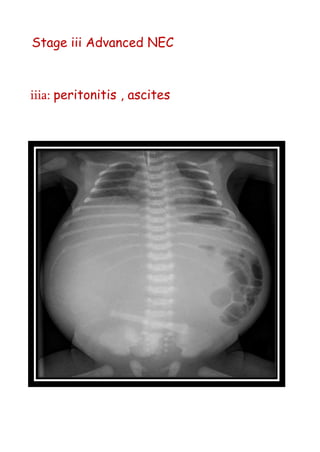

Stage iii AdvancedNEC iiia: peritonitis , ascites

Stage iii Advanced NEC

iiia: peritonitis , ascites